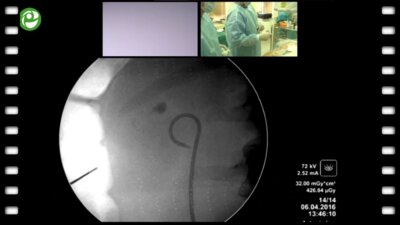

Мастер-класс по перкутанному лечению камней почки

06 апр 2016

3094 просмотра